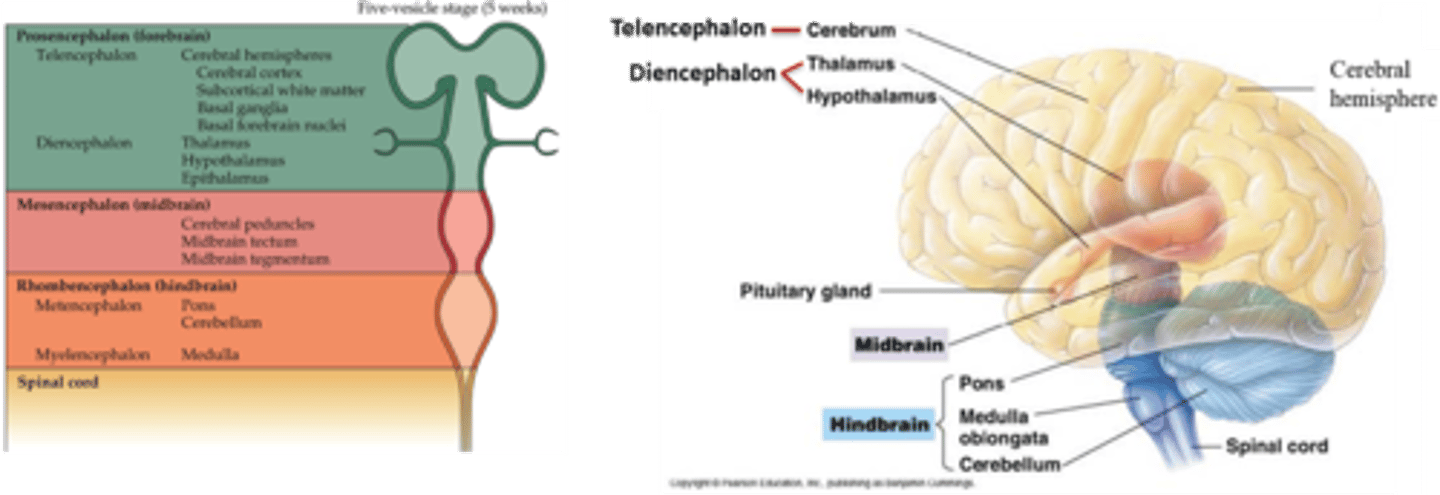

what are the 3 primary brain vesicles and the 5 secondary brain vesicles?

1. prosencephalon (gives rise to the telencephalon and diencephalon)

2. mesencephalon (gives rise to the midbrain)

3. rhombencephalon (gives rise to the metencephalon and myelencephalon)

what are the 3 regions of the brain?

1. cerebrum (cerebral hemispheres)

2. brainstem

3. cerebellum

what are 2 important structures of the diencephalon?

1. thalamus

2. hypothalamus

what are the 3 parts of the brainstem?

1. midbrain

2. pons

3. medulla